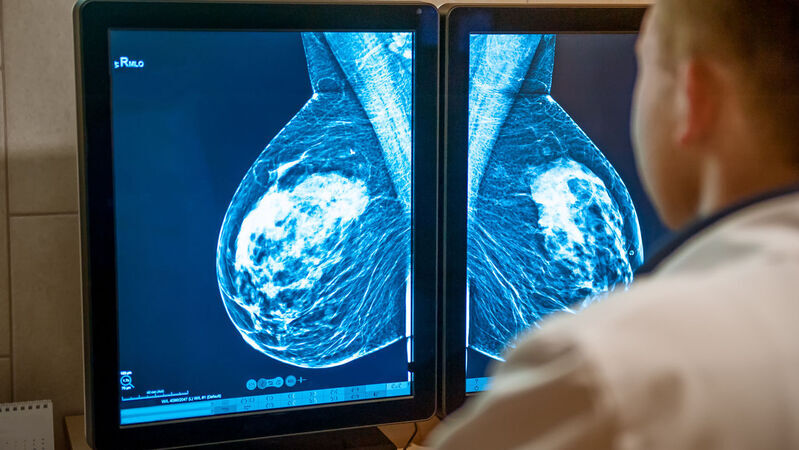

Lo studio Destiny Breast-06 su 866 pazienti, presentato in sessione plenaria al congresso della American Society of clinical oncology (Asco) in corso a Chicago da Giuseppe Curigliano, membro del direttivo nazionale Aiom (Associazione Italiana di Oncologia Medica), dimostra che circa il 90% di loro può essere trattata con questo farmaco mirato, anche quando la proteina HER2 è presente in quantità estremamente basse.

I risultati dello studio Destiny evidenziano l’importanza di determinare con precisione lo stato di Her2.

In questo senso, è fondamentale il ruolo del team multidisciplinare nei centri di senologia, in particolare la collaborazione tra oncologo e patologo che effettua i test diagnostici per definire il profilo molecolare.